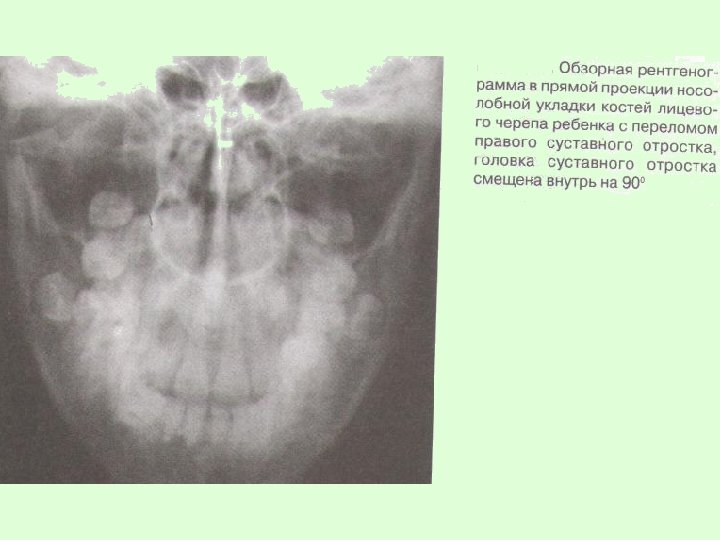

Заключительный диагноз перелома нижней челюсти ставят после проведения рентгенологического исследования в боковой укладке по Генишу или обзорной рентгенограммы нижней челюсти в прямой проекции, при переломе суставного отростка – ортопантомограммы или рентгенограммы сустава по Шуллеру или Парма.

На рентгенограммах обычно определяется нарушение целостности костной ткани, наличие линии перелома, смещение отломков челюсти. В сложных диагностических случаях переломов суставного отростка нижней челюсти у детей для постановки окончательного диагноза при отсутствии явных клинических и рентгенологических признаков используют метод спиральной компьютерной томографии с мультипланарной реконструкцией.